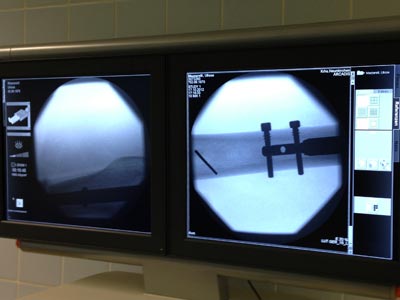

Face à une demande croissante, nous avons depuis 2009 très largement renforcé notre activité médicale.

L'étroite collaboration entretenue avec nos partenaires ainsi que la maitrise des exigences de ce secteur (Normes, Matériaux...) nous permettent aujourd'hui de développer des dispositifs innovants.